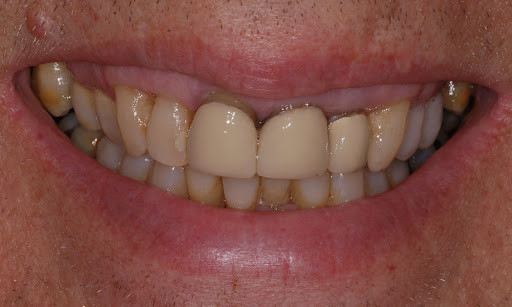

Treatments for a black tooth

Black spots on teeth can be treated quite simply, these can often be caused by a small pit or chip in the tooth which either picks up staining or has a small amount of decay. Your dentist can usually remove a small amount of tooth around this area, removing the staining and/or decay and placing a some tooth-colored bonding material over this area. The tooth bonding will blend in naturally with your surrounding teeth, making the repair invisible.

Dead tooth whitening is also possible. This is whitening with a peroxide gel which can whiten teeth significantly; however, sometimes teeth whitening alone is not enough to whiten a dead tooth and some form of restorative option needs to be considered, either a dental veneer or a dental crown.